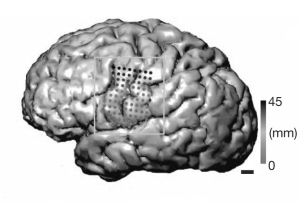

植入癫痫病人大脑的电极揭示了辅音与元音的清晰发音具有完全不同的大脑活动模式。图片来源:Ref 1

一支美国研究团队如今搜集了毫米及毫秒量级的脑活动数据。利用植入患者大脑皮质中的电极――这是例行术前电生理诊断的一部分,研究人员记录了3名癫痫病人的大脑活动。他们随后观察了当病人明确地说出一系列音节时,大脑发生了哪些活动。